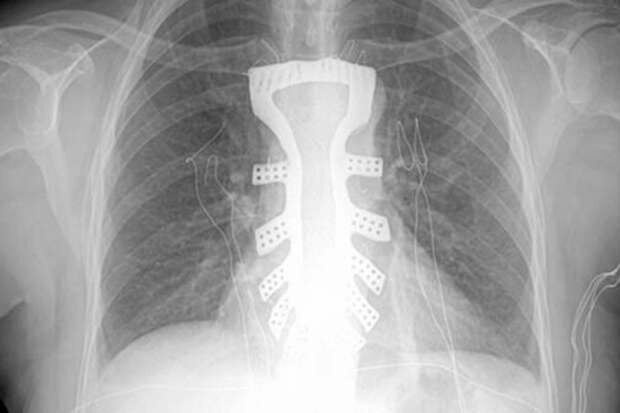

Un equipo médico chino implantó con éxito un esternón de titanio fabricado con una impresora 3D a una mujer que padecía un tumor en ese hueso, en la primera operación de este tipo que se realiza en el país.

Los médicos dedicaron medio mes a diseñar el esternón de Gu y solicitaron la ayuda de un laboratorio especializado de la Universidad Politécnica del Noroeste para imprimirlo con tecnología 3D.